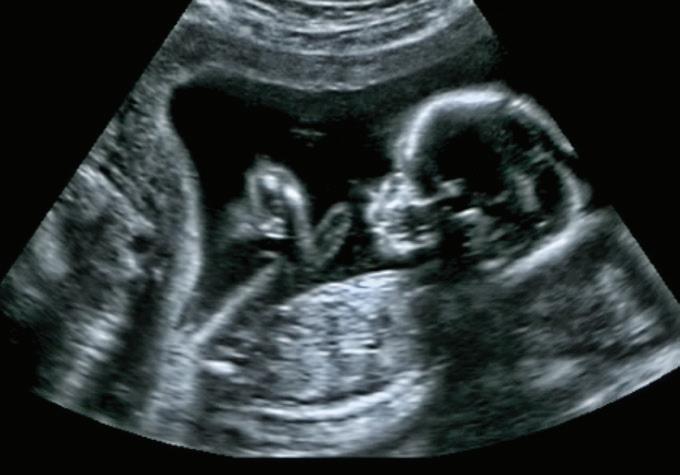

Preterm BIRTHS

Premature births (less than 37 weeks gestational age) result in increased health challenges that can persist throughout childhood and into adulthood. Children who were born preterm are more likely to struggle with asthma, pulmonary disease and neurologic problems (such as developmental delay and cerebral palsy). Preterm birth is also associated with increased incidence of high blood pressure, heart disease, asthma, Type 2 diabetes and increased mental health problems as adults.11

Approximately 10.1% of children in the United States and 10.8% of children in Texas are born prematurely. In Northeast Texas, 11.0% of children are born early. While this average is not strikingly higher than state averages, 22 of the 42 counties within the region have rates above the state average. Eleven counties have premature birth rates higher than 12%. In Bowie County, 13.5% of children are born prematurely. These elevated rates of prematurity increase the need for pediatric health resources in these areas.12